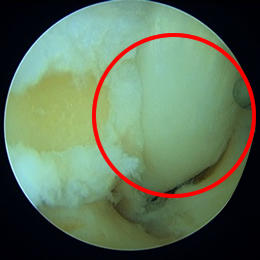

保存療法では痛みが取れない場合には、手術療法が選択されます。手術では主に内視鏡を使用して三角骨の摘出、並びに長母趾屈筋腱の腱鞘の切開を行っています。

内視鏡の手術では腹臥位(うつ伏せ)で行います。アキレス腱の両側に7mm程度の傷をつけるだけで手術を行うことができます。手術中に足関節後方の滑膜炎の程度(痛み具合)や長母趾屈筋腱の障害の程度を評価し、一人一人の状態に合わせたリハビリを行っていきます。平均して10日~2週間程度入院します。退院後も再発しない様に、体の正しい使い方などを指導していきます。

![]() 三角骨による圧迫 |

![]() 長母趾屈筋腱腱鞘を開放した後 |